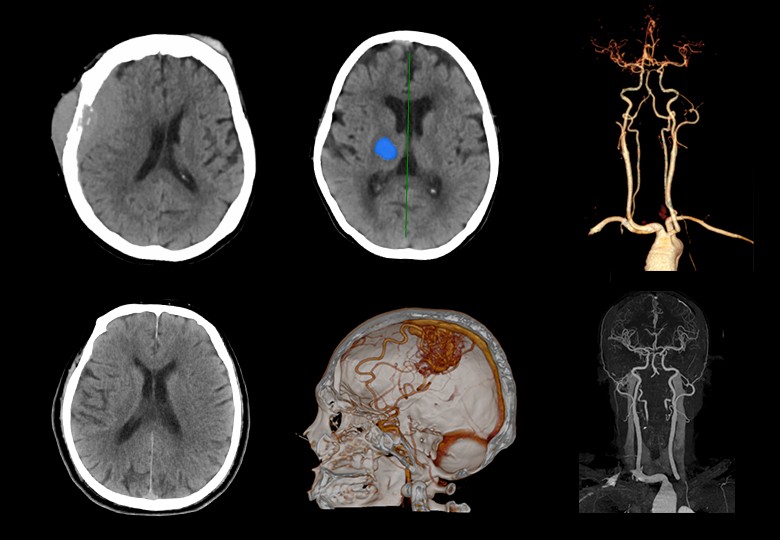

Album d'images cliniques

• Tête